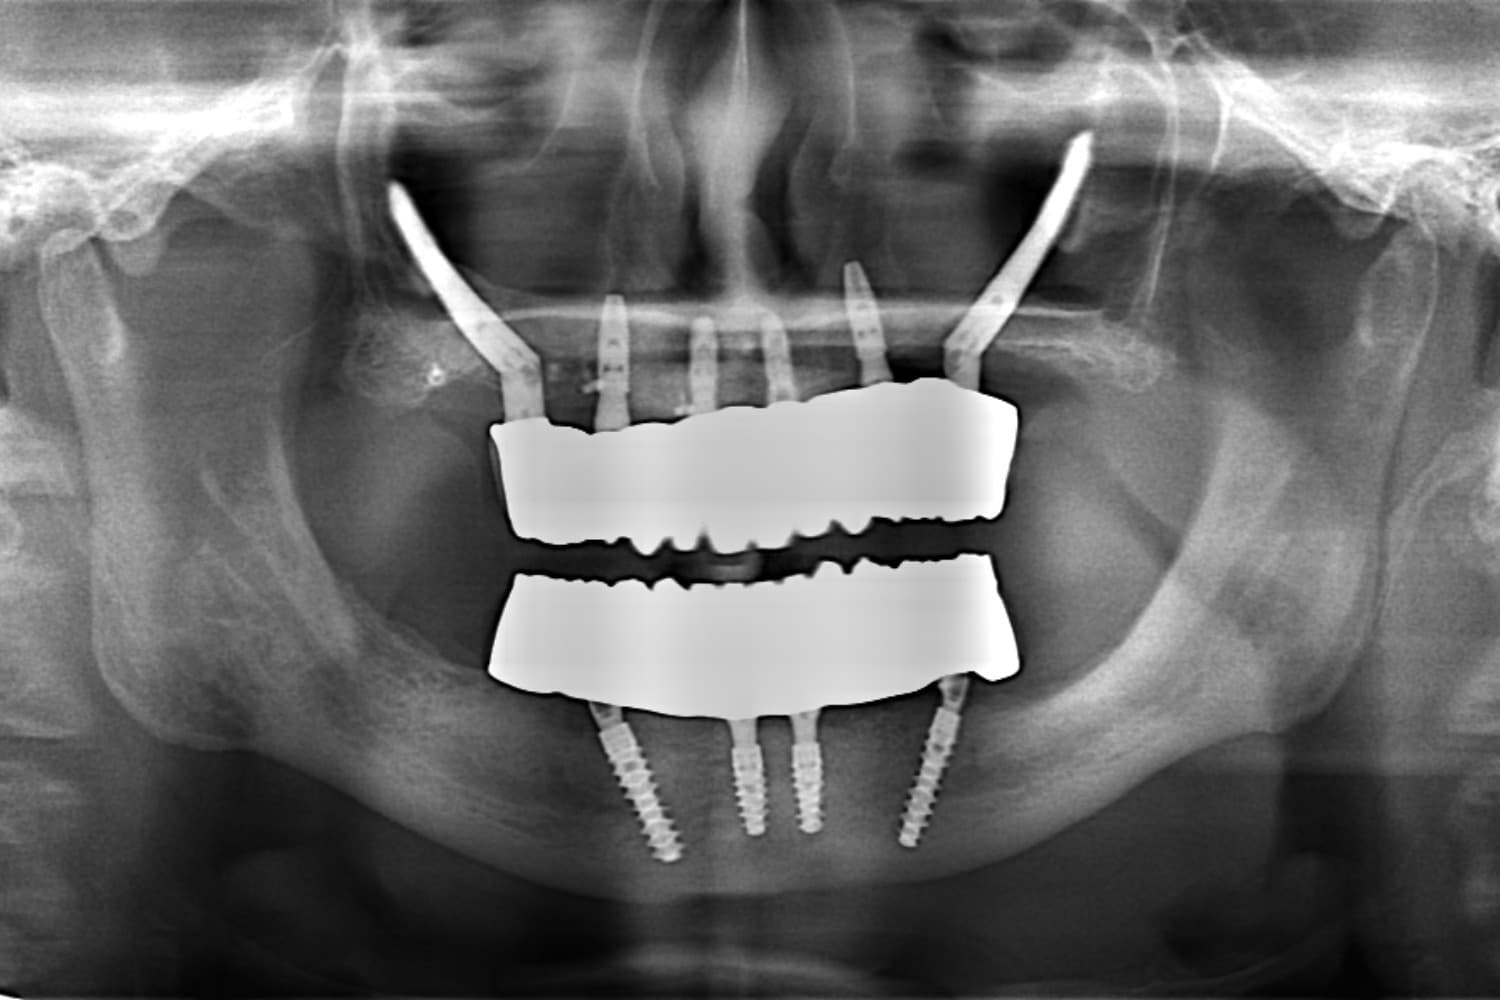

Before

重度の歯周病で上下すべての歯を抜歯せざるを得なくなった患者さまに対して、上下顎オールオン4で治療を行った。

年齢

70代

性別

男性

主訴

入れ歯が合わない 噛みにくい

治療期間

6カ月

治療回数

15回

費用

7,432,000円

副作用・リスク

清掃状態等により将来炎症を起こす可能性があります。